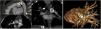

A CTA was then deemed necessary, which demonstrated the presence of an occluder in the aforementioned area, eliciting stenosis in both vessels (Figure 2, Video 7)